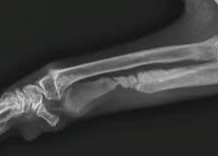

悪性骨腫瘍のなかで、家畜に多発するものは骨肉腫(osteosarcoma)です。

骨肉腫は壮老齢の犬、とくに大型犬の四肢の長骨・肋骨に発しやすく、通常悪性度が高く、しばしば肺に転移し、動物は悪液質に陥って斃死するものが多い。

四肢の場合は、早期に断脚術を行ったものは予後は比較的良好ですが、一般に再発することが多く、また転移病巣の多いもの、あるいは手術不能の部位のものでは、予後不良です。